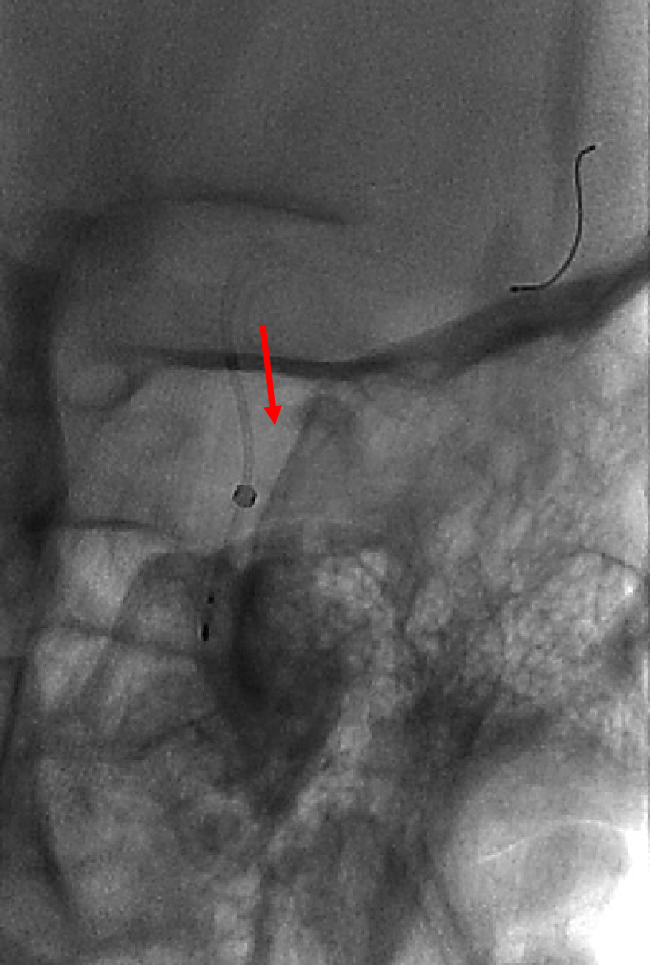

术后图像显示支架打开及贴壁良好。

术后工作位造影

术后侧位造影

术后正位造影

术后患者一般情况可,诉头疼,给予对症处理。神经查体:无阳性定位体征。给低分子肝素4100U皮下注射一次。继续口服阿司匹林100mg 1次/日,替格瑞洛90mg 2次/日。